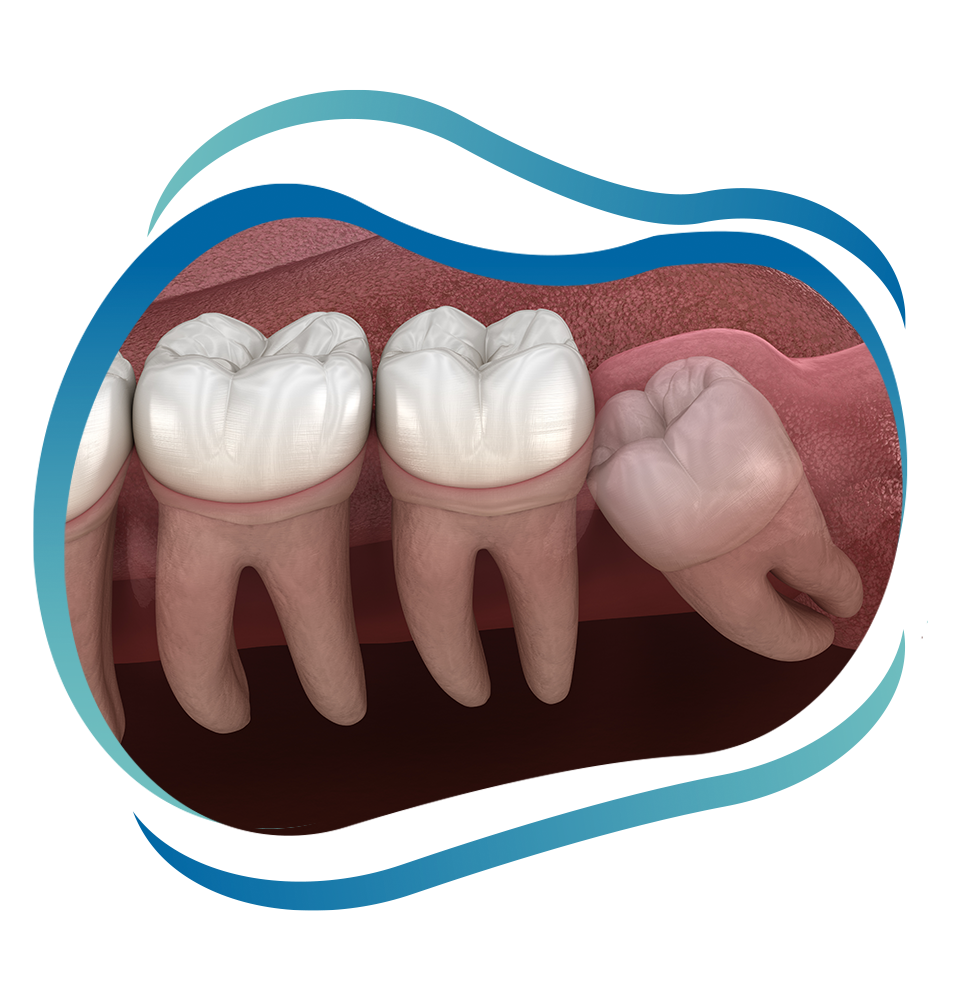

In some cases, wisdom teeth, or third molars, may be able to join existing teeth and become a permanent part of your mouth. Other times, you may experience pain and your oral health may suffer due to common, but treatable, complications. We know that erupting at an angle, only emerging partially and damaging surrounding teeth can lead to severe pain, infection and eventually the need for wisdom teeth extractions. That’s why we do everything possible to offer highly trained and technologically advanced techniques to diagnose and treat these issues quickly and comfortably. Our oral surgeons not only have over 50 years of combined experience offering numerous oral surgical procedures but have extracted thousands of wisdom teeth in and around Manchester and West Hartford, CT. We also offer sedation options like nitrous oxide, IV sedation and opioid-free pain management for your comfort. A routine and highly common procedure at our practice, we still take pride in making wisdom teeth extractions personalized to your needs and specific situation.

Wisdom teeth typically emerge between 16 and 25 years of age. Although it’s best to remove them in your teen and early adult years, wisdom teeth may not cause pain until later in life. Many patients don’t experience symptoms, even if they have impacted teeth. When wisdom teeth are impacted, they are blocked and are unable to fully erupt. We use our i-CAT® Cone Beam CT imaging technology to capture three-dimensional and detailed images of your teeth and their surrounding oral structures to grasp a thorough understanding of your current state before recommending your custom care. If impacted wisdom teeth extractions are advised, we will carefully remove them while you are comfortably sedated and provide detailed instructions for how to encourage healing.

Common Symptoms of Impacted Wisdom Teeth

- Impacted Wisdom Tooth